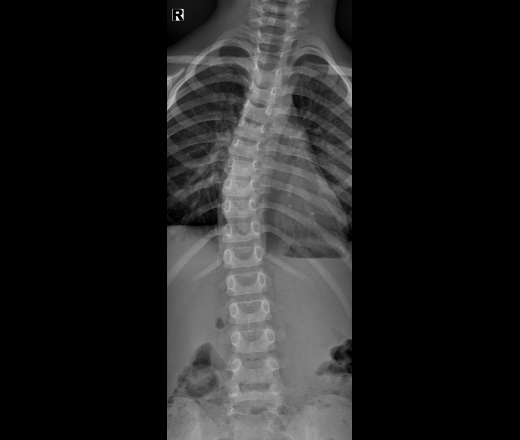

Пол пациента: Мужской пол Тип патологии: Другое Область исследования: Скелетно-мышечная система Методы исследования: Rg Здравствуйте,как расценить изменения в3 -м грудном позвонке,3 года,сколиоз,спасибо https://radiomed.ru/sites/default/files/styles/case_slider_image/public/user/53523/2_1_3.jpg?itok=3hQAWP5O ID:88941 Цель публикации: Консультация Mon, 01/11/2021 - 18:48 #1 NIL Offline Last seen: 1 month 4 days ago Joined: 25.11.2013 - 20:50 Posts: 18208 Позвонки ротированы. Других изменений не нахожу. "Слушай всех, прислушивайся к немногим, решай сам".© Mon, 01/11/2021 - 19:49 #2 Евгения ДОКТОР Offline Last seen: 3 months 2 days ago Joined: 11.07.2021 - 12:21 Posts: 129 Спасибо большое Вам

Позвонки ротированы. Других изменений не нахожу.